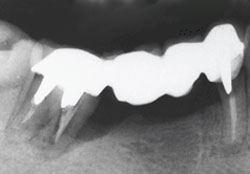

Bridges become a less sensible option in this situation. The longer span of the bridge puts even more pressure on the teeth they are attached to, requiring additional teeth be crowned to keep it stable. This creates an even less hygienic situation, leaving the teeth more vulnerable to decay and bone loss (the following x-ray illustrates this), which increases the bridge’s potential failure and the likelihood for more expense and time in the dental chair.